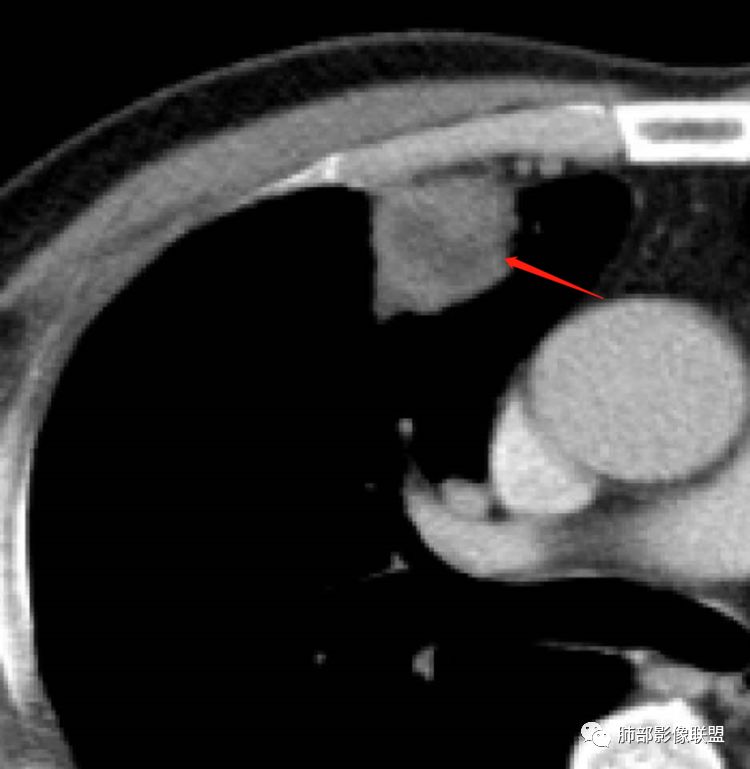

患者,男,52岁主诉:咯血6小时既往史:否认高血压、糖尿病等。定位在哪?

水平裂以上,上叶前段,先看周围,非远端有斑片状高密度影。

边缘平直、稍凹陷,部分区域膨隆。

宽基底与胸膜相连,附近胸膜稍增厚。

支气管进入病灶内,近端堵塞,断端圆钝。

支气管壁均匀稍增厚。

回顾性分析本病例,小编觉得鉴别诊断聚焦于肺鳞癌和炎性病灶(包括结核)之间,这个病灶的炎性征象大于恶性征象;以下是这个病例的的炎性征象:①病灶边缘平直收缩为主,也缺少典型的分叶毛刺;②支气管走行于病灶中央截断,断端比较圆钝;③近端引流支气管壁增厚;④整体强化不显著,坏死区太圆太规整,边缘隐约显示强化的环;⑤血管走形自然,未见明显破坏征象;⑥胸膜外脂肪间隙增宽,胸膜广基地增厚,未见栽赃;⑥52岁偏年轻(此条也不大支持鳞癌)

虽然本例患者支气管截断,病灶中央截断炎性及恶性都可以,断端向病灶一侧圆钝更支持炎性。